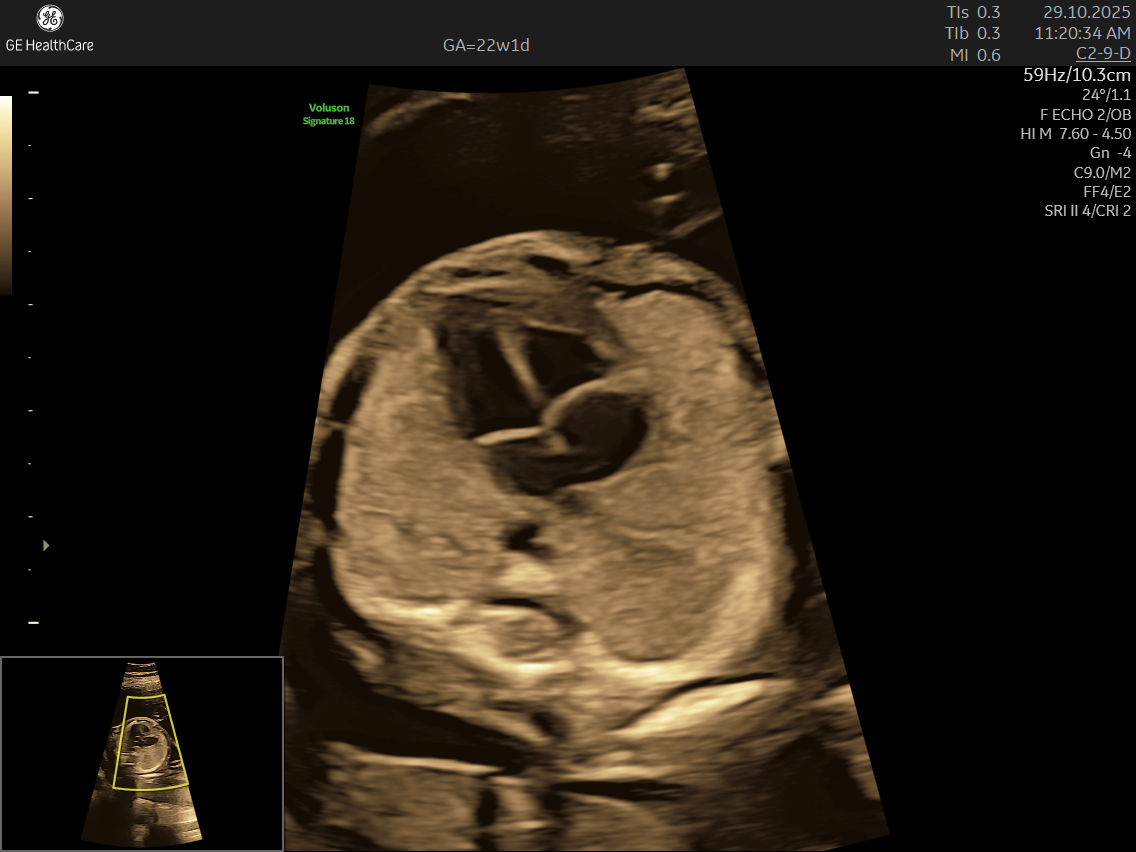

- Focus on the Heart: This scan is dedicated solely to assessing your baby’s heart—its structure, blood flow, and rhythm—offering a far deeper evaluation than standard ultrasounds.

- Specialized Equipment and Expertise: Performed with high-resolution machines and by specialist doctors, fetal echocardiography pinpoints tiny structural or functional abnormalities that conventional scans may miss—helping ensure early, accurate diagnosis and informed planning.

- Structural Defects: Such as septal defects (holes in the heart), valve abnormalities, and underdeveloped chambers.

- Its a specialized ultrasound done between 18–24 weeks of Gestational Age that evaluates the structure, function, and rhythm of a baby’s heart while still in the womb. This scan uses high-frequency sound waves to create detailed images of the fetal heart, aiding in the detection of congenital heart defects (CHDs) and other abnormalities.